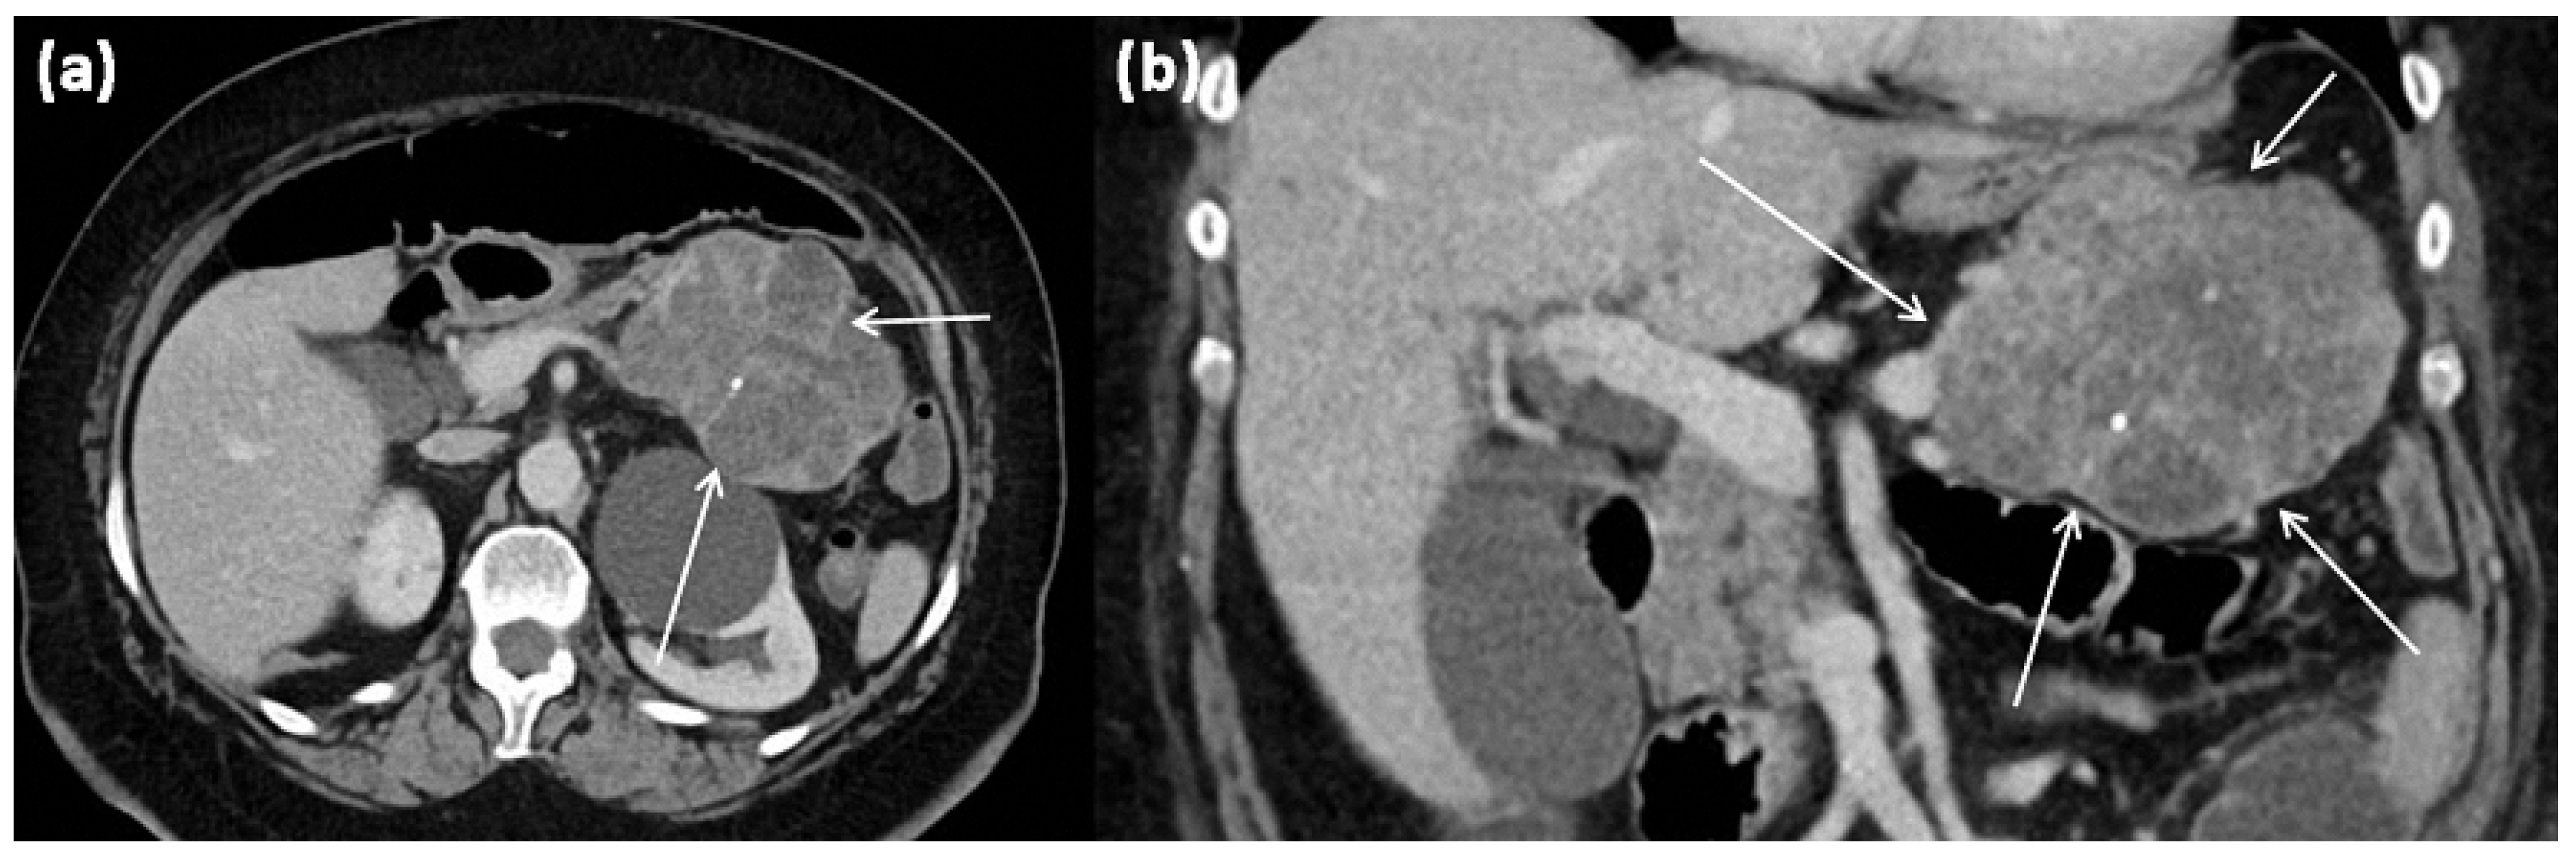

Figure 16.

MRI of a 60-year-old patient with a partly cystic and partly solid mass of the pancreatic tail. Arterial T1w after gadolinium-based contrast administration (a) typical peripheral hyperarterilization (arrows) can be seen. In T2w, solid as well as cystic parts are present (b).

The extremely rare variant of a solid SCN is a differential diagnosis to neuroendocrine tumors (NET) (Figure 16 and Figure 17). In this case, the diagnostic criterion was shown to be the contrast agent behavior, which typically does not show washout in NET and can be observed more frequently in solid SCN []. The contrast behavior of NET is variable; in unclear cases, EUS-guided biopsy should be weighed to exclude NET.